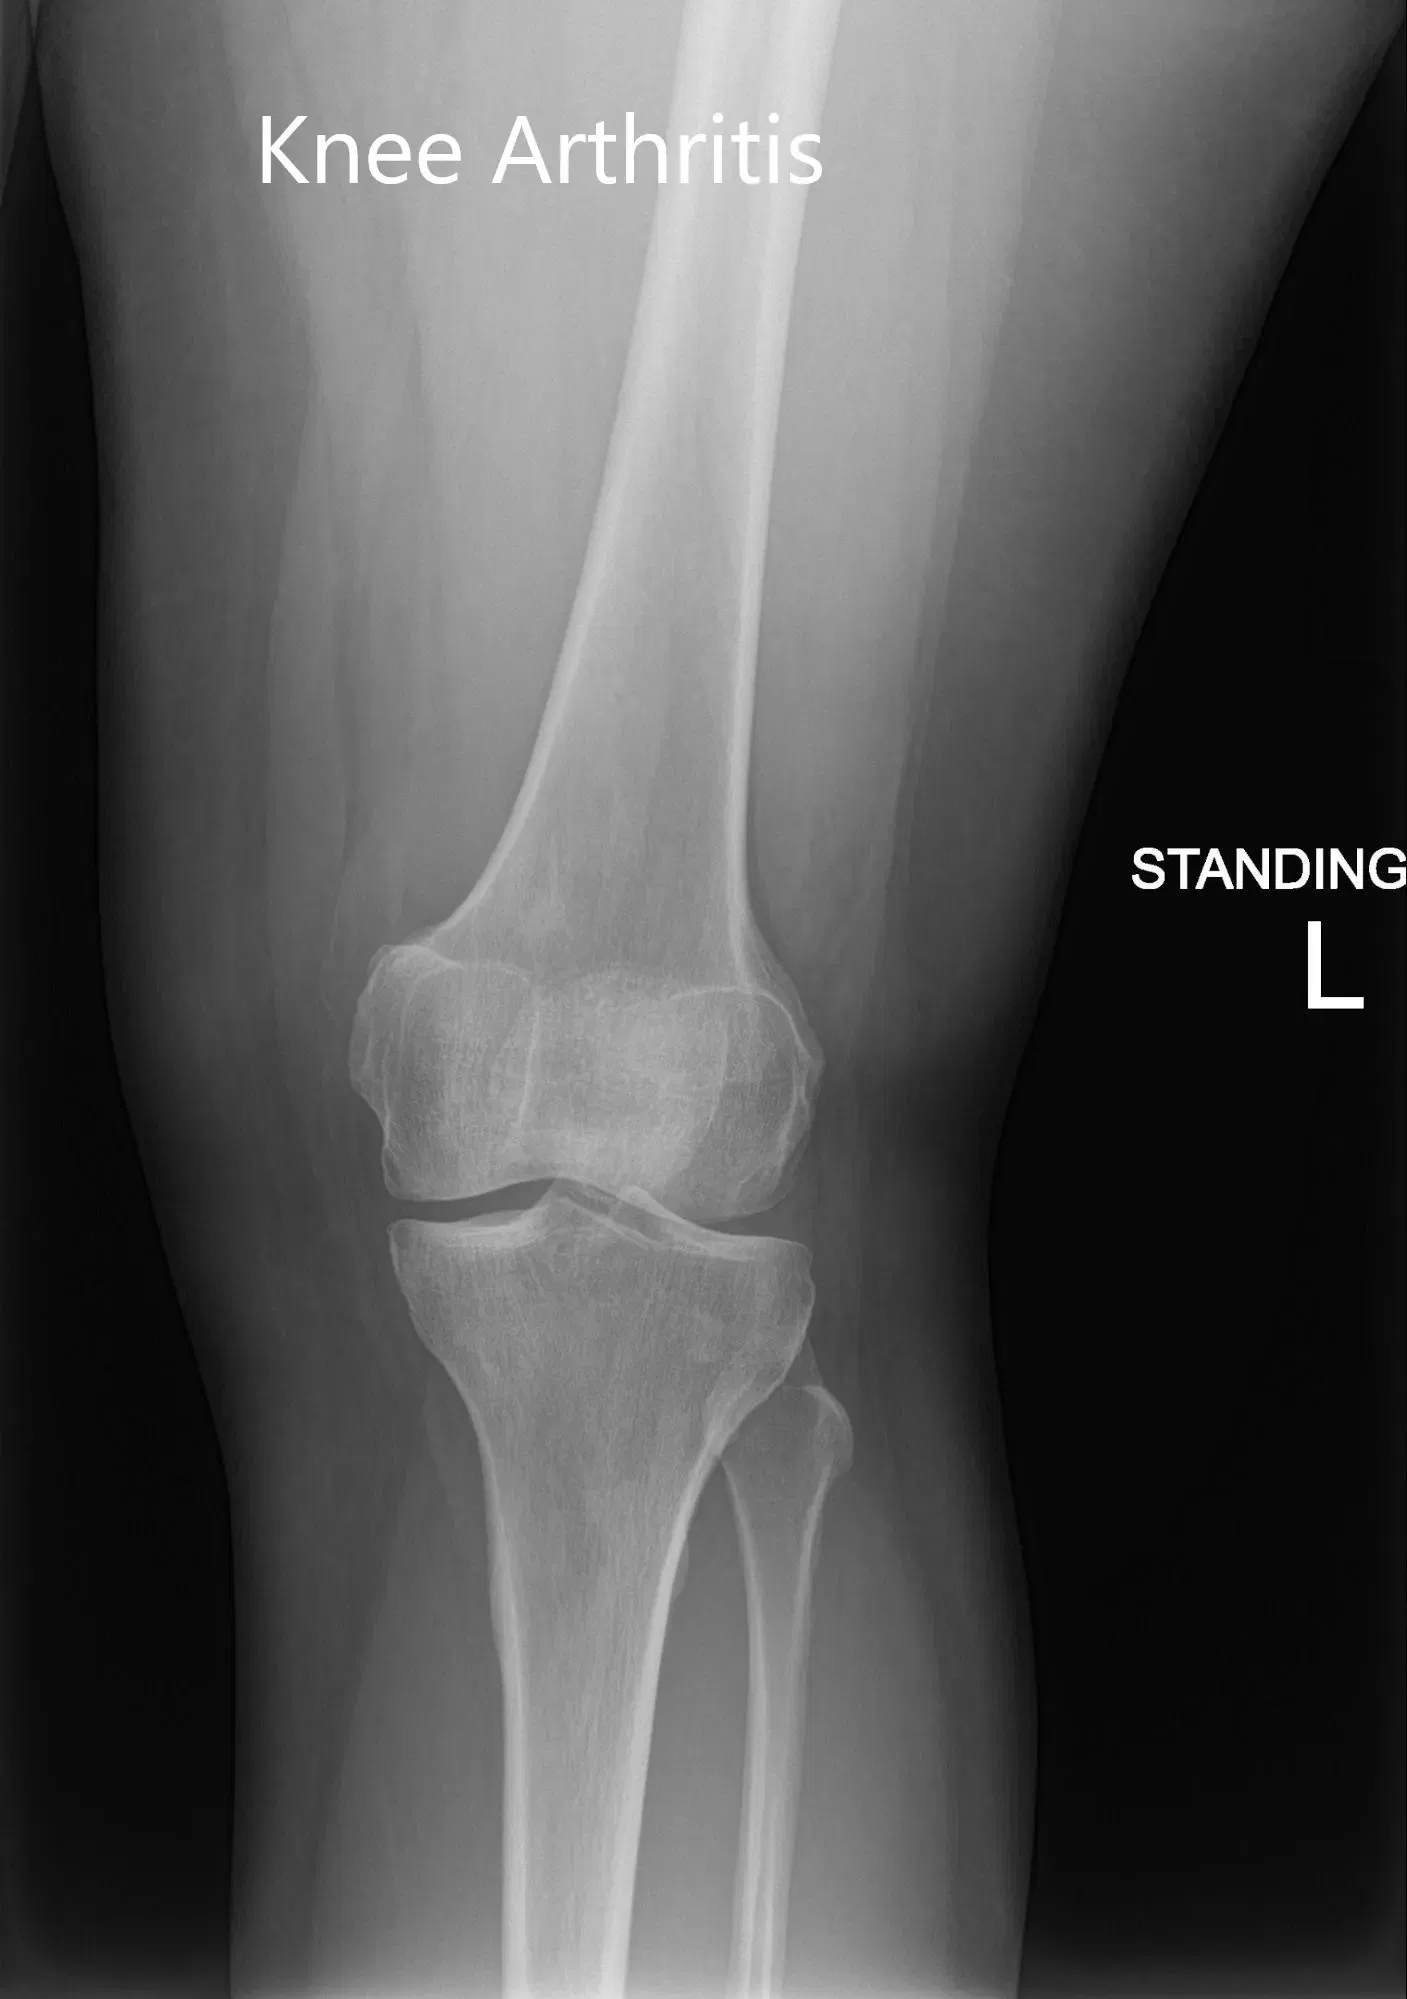

Su examen físico reveló sensibilidad en la línea articular medial con inflamación leve. La rodilla no mostró inestabilidad en las pruebas de esfuerzo anterior, posterior, valgo y varo. Las imágenes revelaron artritis postraumática en la rodilla izquierda. Le pusieron una inyección de cortisona en la rodilla con un excelente control del dolor. Posteriormente, el paciente fue seguido en 3 meses.

Radiografía preoperatoria de la rodilla izquierda que mostró imágenes AP y laterales